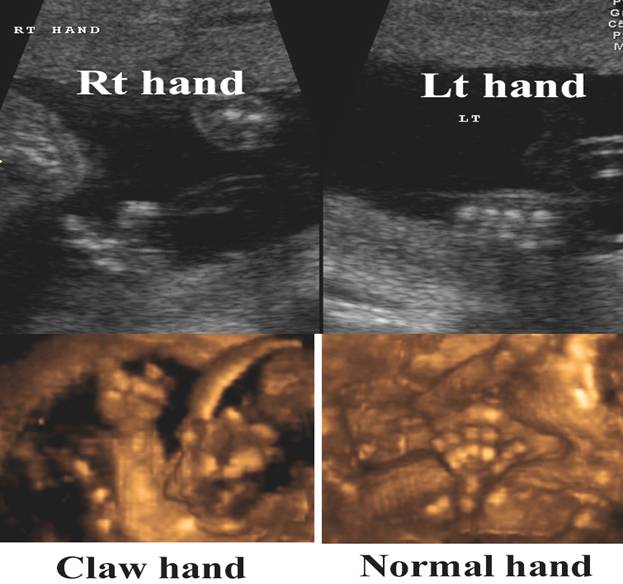

Isolated claw hand – 2nd  + 3rd digits missing. Soft tissue and osseous syndactyly 4th +5th  fingers

Lobster claw with absence of central rays dividing the hand into two parts